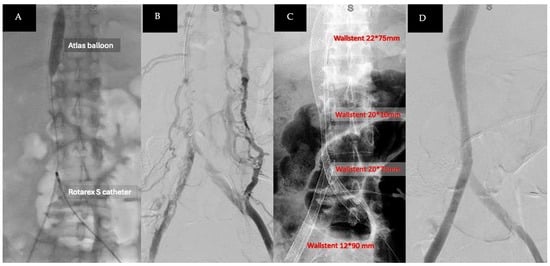

2. Detailed Case Description